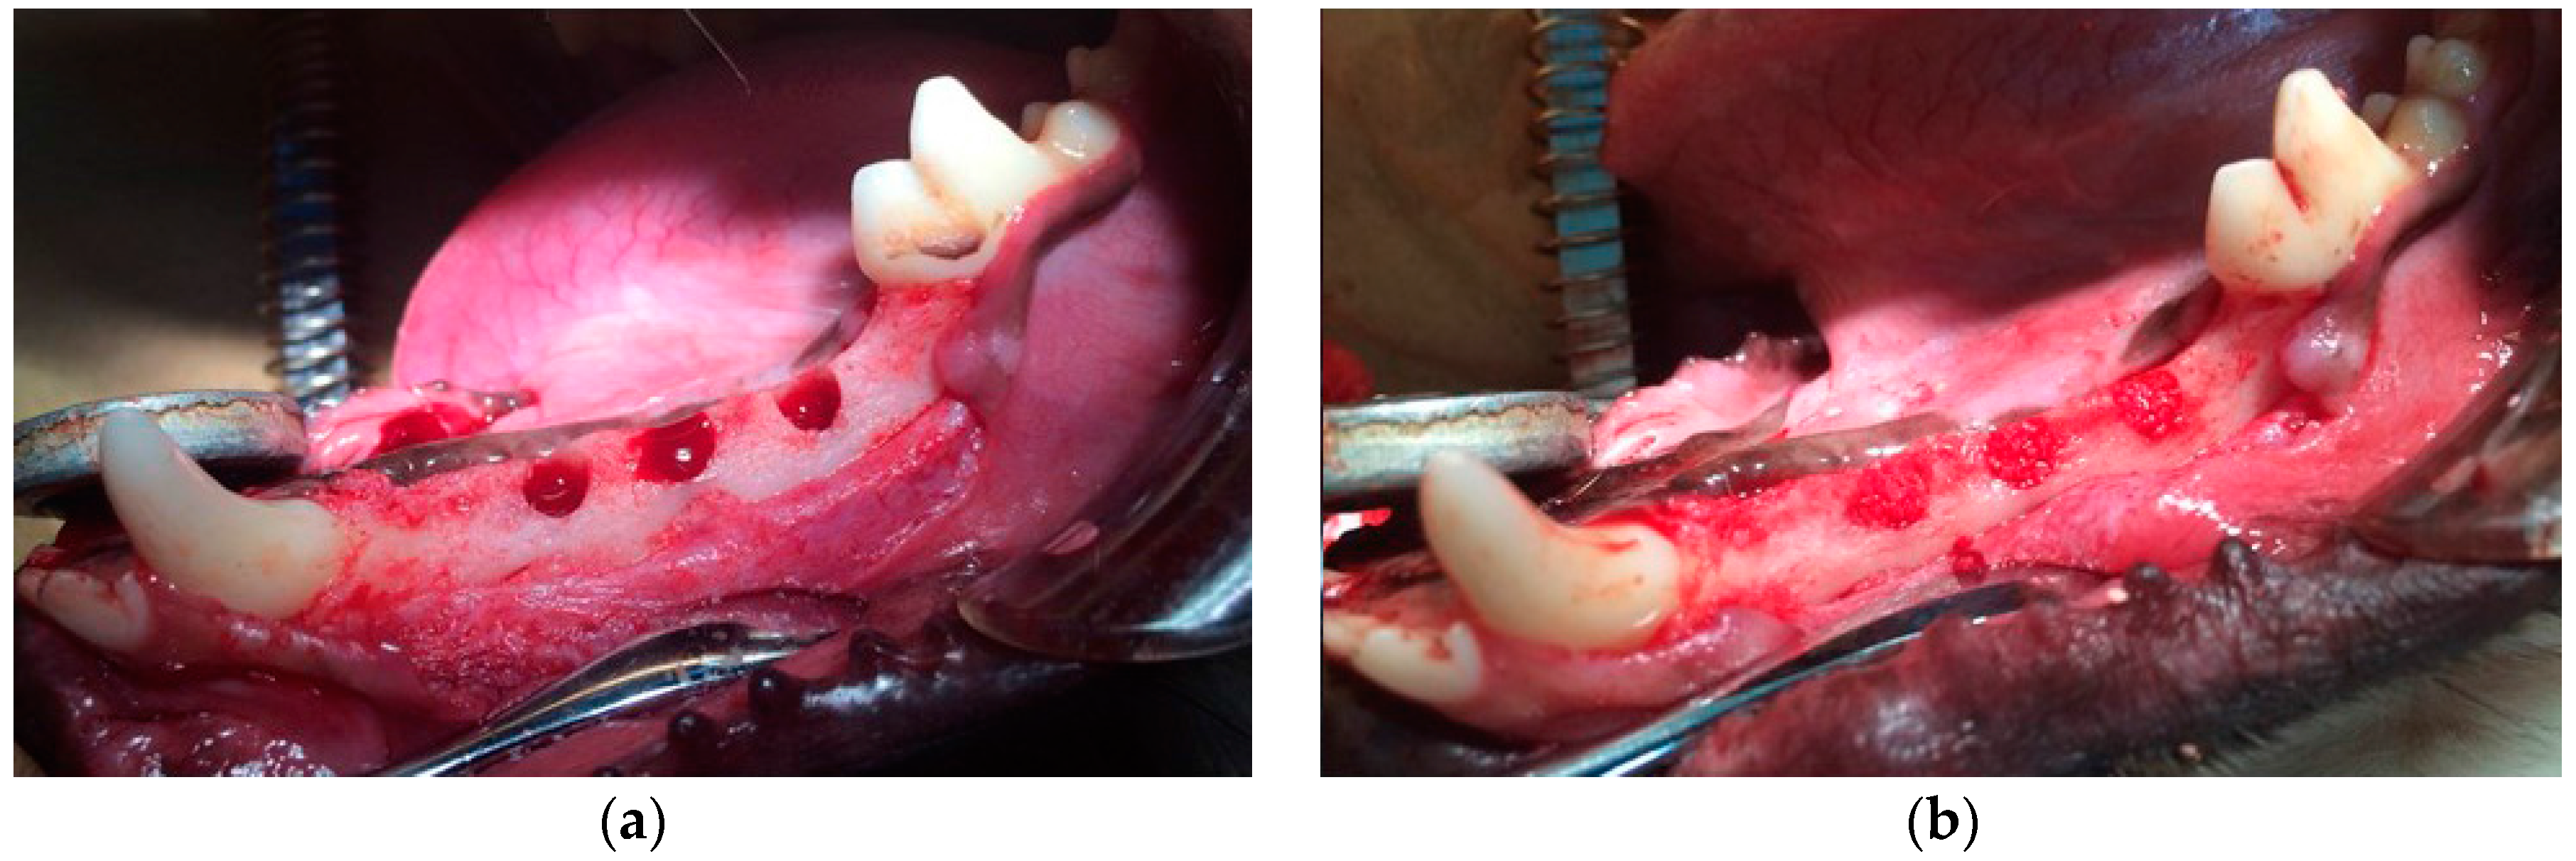

All procedures in this study were approved by the Animal Experiment Committee of Osaka Dental University and conformed to those described in the Guiding Principles for the Use of Laboratory Animals (approval Nos. 12-12001 and 13-03026). The first to fourth premolars were extracted to create space for identical defects 2 months prior to the treatment. An initial incision was made to the squamous epithelium of the gingiva that covered an appropriate part of the mandible, and the subcutaneous tissue was separated from the periosteum. A second incision was made in the periosteum of the mandible, which was lifted and carefully dissected from the underlying mandible. Identical defects (diameter: 4.5 mm, depth: 6 mm) were then made using a twist drill (Astra Tech, Tokyo, Japan) with physiological saline cooled under general anesthesia (0.5 mg/kg pentobarbital sodium) and infiltration anesthesia (1.8 mL of 2% lidocaine hydrochloride and 1:80,000 epinephrine) (Figure 7a). The defects were randomly filled with one of two treatments: bFGF bound to porous α-TCP via heparin, or unmodified porous α-TCP (control) (Figure 7b). The defects were assessed two, four or eight weeks after surgery. The periosteum and skin overlying the defects were sutured in two layers with 3-0 Vicryl (Ethicon GmbH & Co. KG, Norderstedt, Germany) and 3-0 MANI Silk (MANI, Tochigi, Japan). The anti-inflammatory agent Carprofe (CarprodylVR; Ceva, Libourne, France) was administered daily for 7 days following each surgery (tooth extraction and implantation). Six cavities per group were histologically analyzed at each follow-up time point.

Figure 7. Photographs of (a) surgically created and (b) treated identical defects.